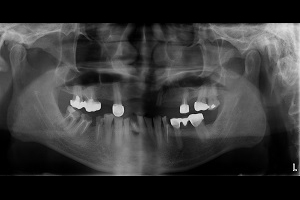

• 病患:55歲先生。

• 主訴:多顆缺牙,想全口治療。

1. 多顆缺牙、牙周病、多顆蛀牙。

治療前-多顆缺牙及牙周病、蛀牙